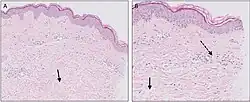

Micrograph of urticaria. Dermal edema [solid arrows in (A, B)] and a sparse superficial predominantly perivascular and interstitial infiltrate of lymphocytes and eosinophils without signs of vasculitis (dashed arrow).[27]

Diagnosis is typically based on the appearance.[2] The cause of chronic hives can rarely be determined.[28] Patch testing may be useful to determine the allergy.[2] In some cases regular extensive allergy testing over a long period of time is requested in hopes of getting new insight.[29][30] No evidence shows regular allergy testing results in identification of a problem or relief for people with chronic hives.[29][30] Regular allergy testing for people with chronic hives is not recommended.[28]